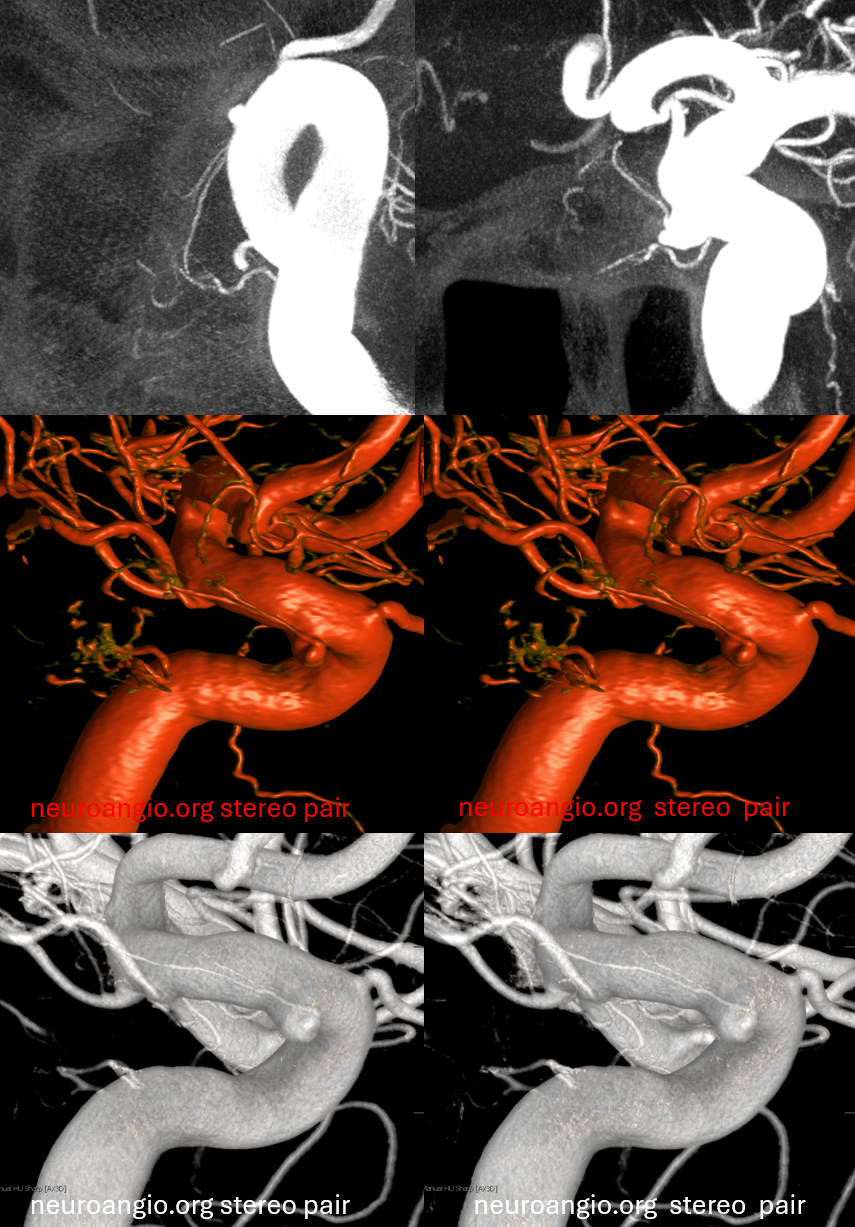

Stereos and MIPs. Both superior and inferior hypophyseals are well seen. The superior hypophyseal, despite being invisible on standard issue views, is quite large, even having two branches to the hypophysis.

Case courtesy Dr. Eytan Raz — here is a beautiful example of a very dominant superior hypophyseal artery (arrow) supplying the posterior hypophysis (arrowhead), with a correspondingly small inferior hypophyseal contribution from the MHT (dashed arrow)

Cross eye stereo

View from the back — again small inferior hypophyseal, big superior hypophyseal — balance again… See the beautiful vascular ring of the posterior pituitary — the connecting it with the contralateral side

Cross-eye stereo

MIP image shows the sella nicely — and helps prove its posterior pituitary

Pure arrowless images — easier to steal…

Of course, there is an aneurysm here — the branch point camp would point out how this larger than usual branch is a setup for aneurysmal formation. Naturally…

Below is a Volume Rendered typical arrangement — a slender (but still large by its own standards) superior hypophyseal supplies the stalk (and anterior pituitary), while inferior hypophyseal from MHT supply the posterior pituitary.